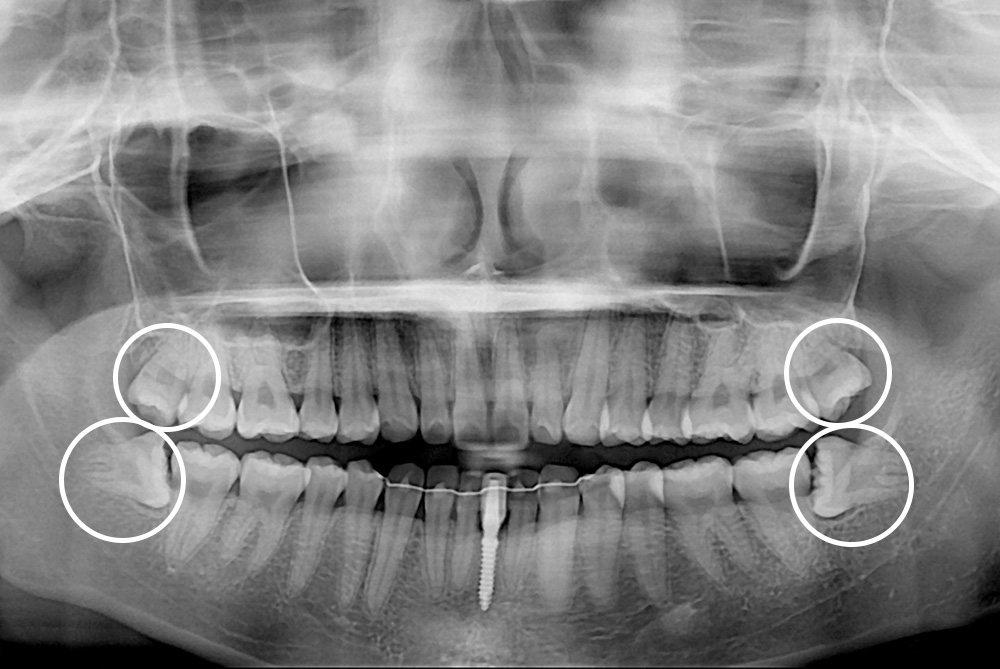

[사랑니] 매복 사랑니 발치

치료전 : 2019-02-19

세종치과는 구강악안면외과학 박사이신 원장님이 발치하는 치과입니다.